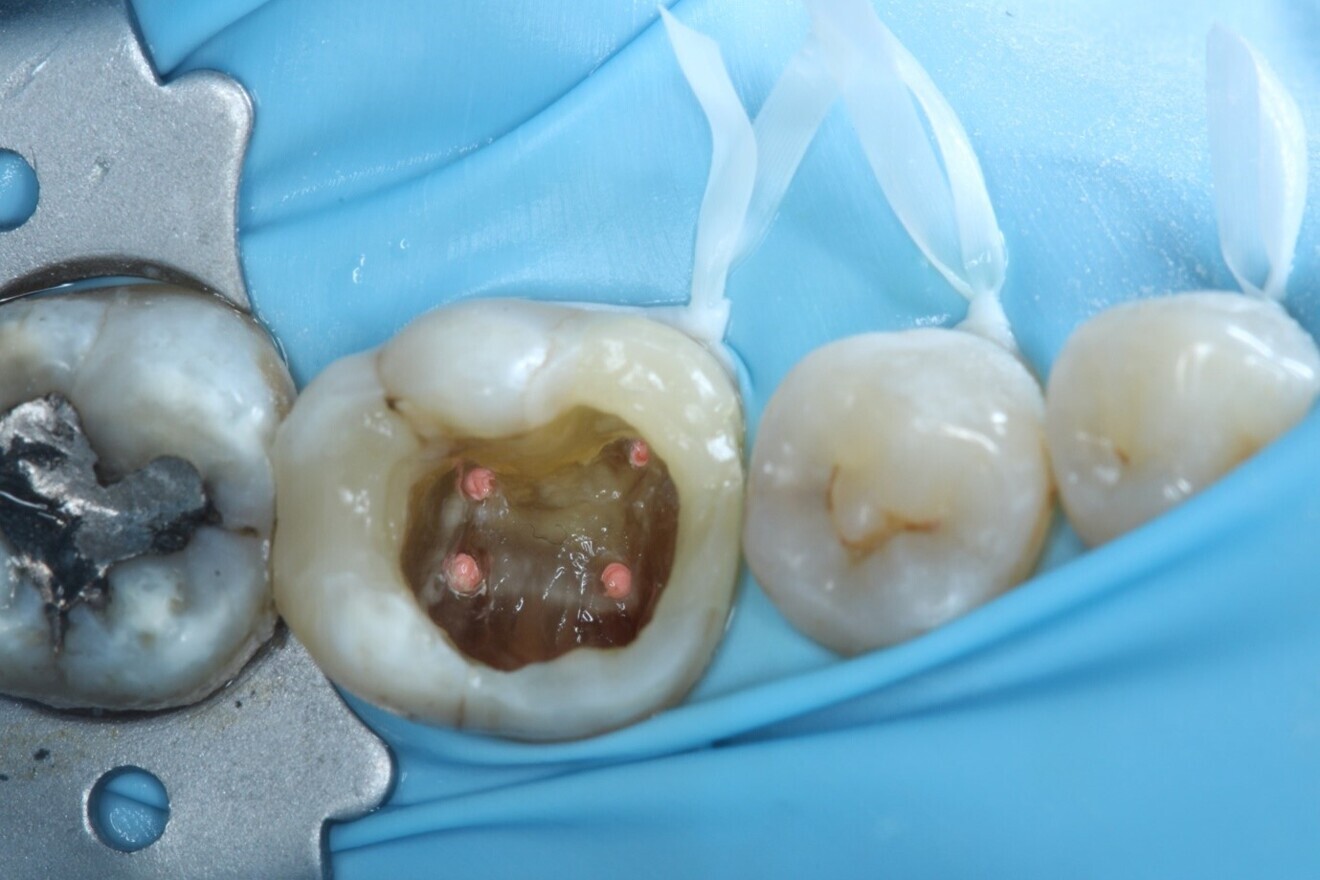

Fig. 2: Dental dam isolation.

Local anaesthesia was administered with 4.4 ml of 2% lidocaine hydrochloride with 1:80,000 adrenaline via buccal infiltration and inferior dental nerve block. A dental dam was placed over teeth #37–34 using a HYGENIC Fiesta #7 clamp (COLTENE) and double floss ties to provide a tight seal (Fig. 2). The tooth was reassessed with caries removal having been carried out (Fig. 3), and four orifices located. The mesial cavity margin was deemed restorable; however, deep marginal elevation would be required. A decision was made to carry out the deep marginal elevation after cleaning and shaping of the root canal system to improve or maintain access to the root canal system.